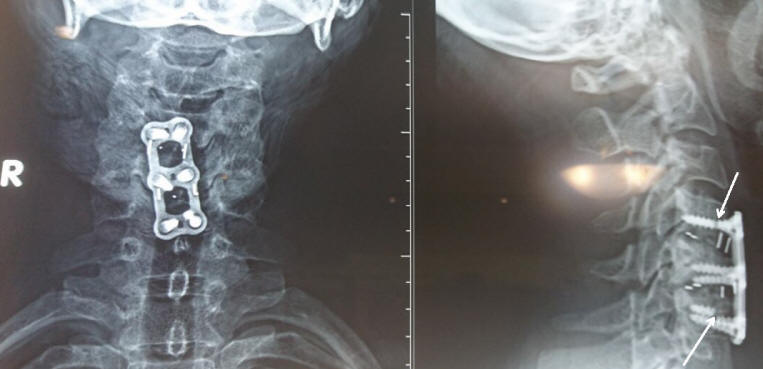

10-JUNE-2014  SAMIA DARWISH AL-BARAGHITHI  48 YEARS PCS C4-5 AND C5-6.

Discectomy of C5-6 and C4-5. During intradiscal removal of C4-5 CSF came out. The head was put slightly down. The discectomy of C4-5 was continued until the dura was seen. There was a pin-point dural defect, which seem that it was adherent to disc material during intradiscal removal. Coagulation of the point did not stop the leak, which hold possibility of presence of other points. The dura was very thin. The CSF leak stopped and a Samarys cervical cage 17x13x5 was inserted to the C4-5 disc space with Stryker BoneSave, which snuggly filled the space to prevent possible postoperative CSF leak. Another cage 17x15x6 mm was inserted to C5-6. Using Trestle cervical plate 2 level 30 mm and 2 fixed 4x14 screws applied to C5 and 2 variable 4x14 mm screws to  C4 and 6, Fusion of C4-5 and C6 done with guidance of C-arm. Routine closure of the wound.

The screws C4 and C6 broken 3 years after the operation with small extrusion of C3-4 (Shown at new MRI). 30-March-2017.